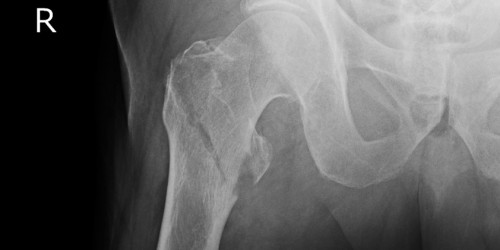

My boyfriend had similar problems. He is a football player and he had strained a muscles or something once which resulted in extreme groin pain. He didn’t do anything about it and let it heal. However, the problem did not go away but it turned into a chronic groin and hip pain.

When he complained to his coach, he went for an ultrasound and had to undergo physiotherapy to have this fixed.

You should also see a doctor and check if you haven’t developed hernia by any chance. If hernia develops in the lower abdomen, it may hurt in the groins as well.